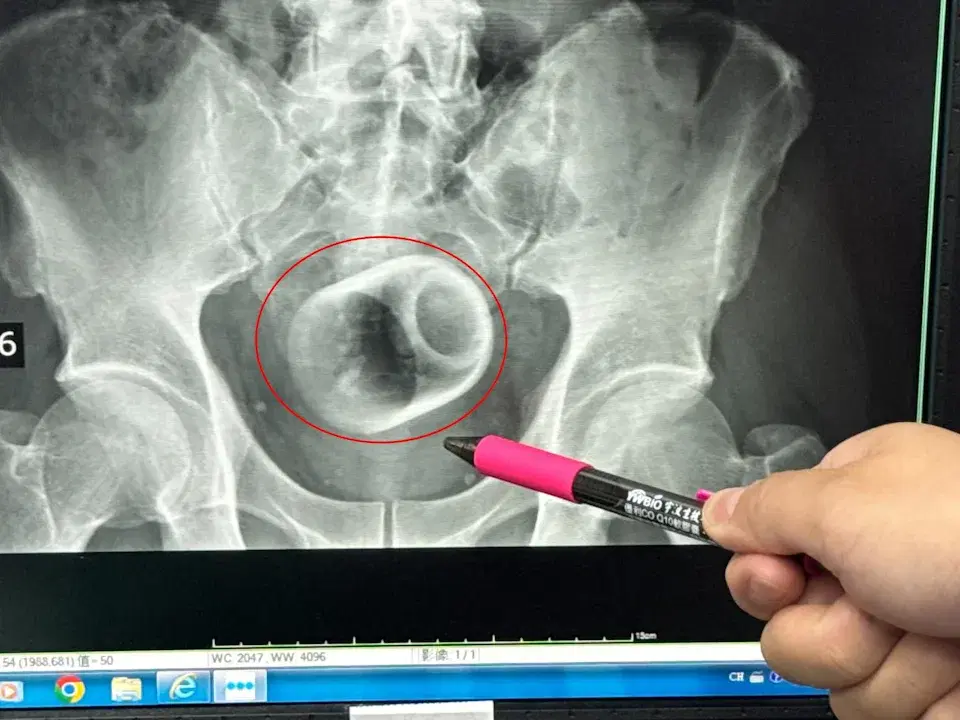

Discovered the ceramic cup during X-ray scan

It wasn’t until an X-ray scan was performed that the medical team discovered a 6cm-wide, 8cm-tall ceramic cup inside the pelvic area, with its opening facing downward.